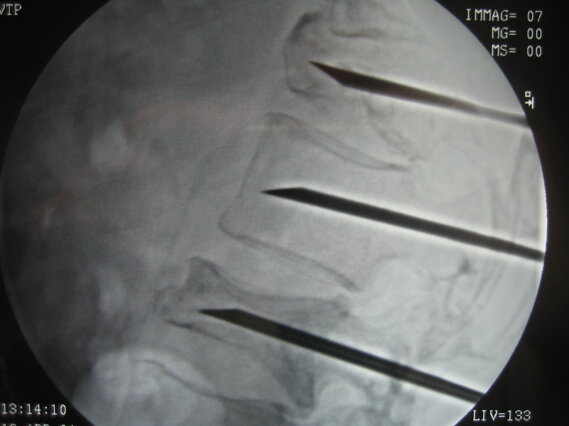

La procedura si esegue in anestesia locale o generale, con guida radiologica. Nella vertebroplastica si inserisce un ago nella vertebra e si inietta cemento osseo per stabilizzarla. Nella cifoplastica, prima di iniettare il cemento, si introduce un piccolo palloncino che viene gonfiato per rialzare la vertebra collassata. La durata è di circa 30-60 minuti.